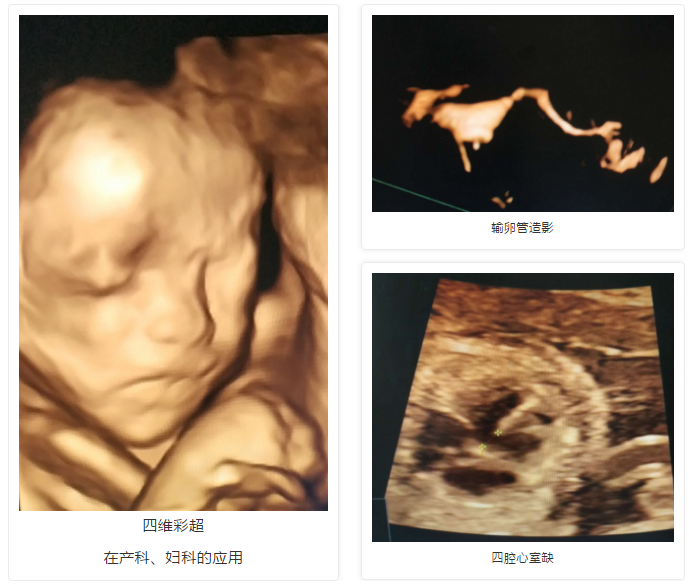

近日,北京安琪妇产医院超声科四维彩超筛查出多例胎儿畸形。3月15日,本院彩超室又筛出一例淋巴水囊瘤合并脐膨出胎儿。据超声显示:胎儿颈背部可见囊性包块回声,内可见明显多房分隔,最宽处厚约1.1cm,皮下可见低回声区,最宽处约0.2cm,前腹壁中线处可见一向外膨出包块,大小约1.3*1.2。超声提示,胎儿淋巴水囊瘤伴皮下水肿、脐膨出,静脉导管A波反向。超声科进行会诊并运用了先进的四维彩超技术,胎儿淋巴水囊瘤和脐膨出清晰可见。

安琪妇产医院超声科采用美国进口的GE-E8高清四维智能彩超,不仅能对产科、妇科、胎儿筛查等方面进行会诊诊断,还能直观、立体、多方位观察孕妇宫内胎儿的活动图像、生长发育情况,高清显示腹中宝宝的实时动态“动画”,直观了解宝宝的一举一动。值得一提的是,准爸爸也可以坐在旁边,一起围观胎宝宝在肚子里面的各种小调皮哦。此外,四维智能彩超在妇科方面也发挥了极大的作用,能够准确的诊断妇产科疑难杂症,尤其在做输卵管造影、观察宫腔息肉方面效果显著。

GE-E8高清四维智能彩超,可直观、立体、多方位观察孕妇宫内胎儿的活动图像、生长发育情况,进一步提高了临床诊断的准确率。